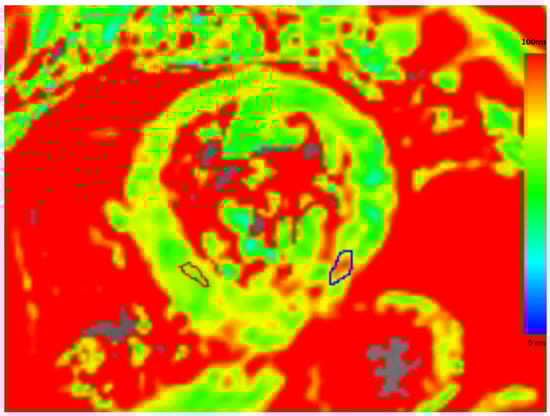

The diagnosis of CS was suspected, based on the recent history of ventricular arrhythmia and sinus arrest in the absence of echocardiographic structural heart disease and hemodynamically significant myocardial ischemia. Laboratory results showed normal inflammatory parameters and normal troponin levels. The patient was admitted for device explantation, performance of cardiac magnetic resonance (CMR), diagnostic invasive electrophysiologic study and upgrade to a dual chamber implantable cardioverter defibrillator. During electrophysiologic study, sustained ventricular tachycardia could be induced. CMR showed prolonged myocardial relaxation up to 62–64 msec on T2 mapping in the inferolateral basal segment of the left ventricle, suggesting acute myocardial inflammation In addition, midmyocardial and subepicardial late gadolinium enhancement (LGE) was demonstrated in the same inferolateral basal segment of the left ventricle (Figure 3 and Figure 4).

Figure 4.

T2 mapping: prolonged myocardial relaxation inferolateral basal segment of the left ventricle up to 62–64 msec.